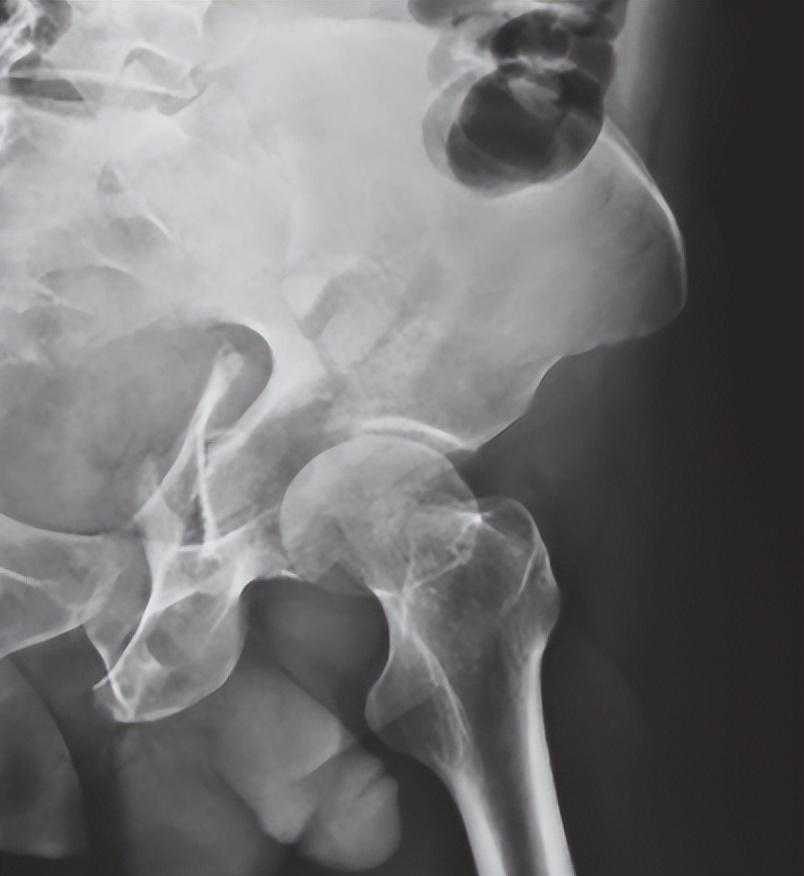

2、骨盆入口位X线检查:

可显示骶骨、髂骨后上部、骶髂关节上方、耻骨联合、耻骨支上缘及髋臼顶弓等。可用于鉴别骨盆环骨折的前后移位、旋转畸形、耻骨联合分离等(图2-3)。

图3骨盆入口位X线片2,可见右侧骶骨翼骨折,耻骨联合分离,提示骨盆前后环损伤,右半侧骨盆向后移位